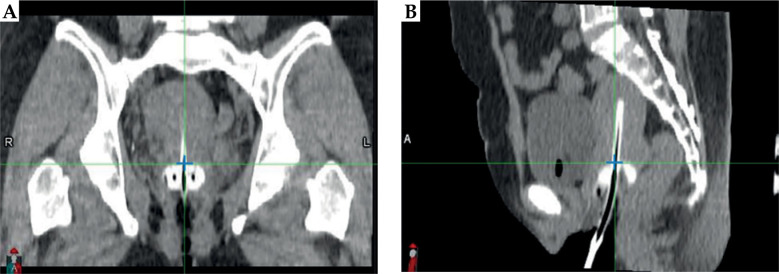

Material and methods: Computed tomography (CT) images, including high-risk clinical target volume (HR-CTV) and OARs structures, were analyzed from 46 treatment plans involving 32 patients undergoing intracavitary brachytherapy with tandem-ovoid applicator, using either traditional fixation (TRD) alone or in combination with patient transfer system (TRD + TS). Applicator displacement was assessed by measuring the distance between applicator base in two sets of CT images: one acquired during treatment planning (pre-plan), and second at dose delivery (pre-load). Dosimetric impact was evaluated for each simulated applicator shift.

Abstract Image